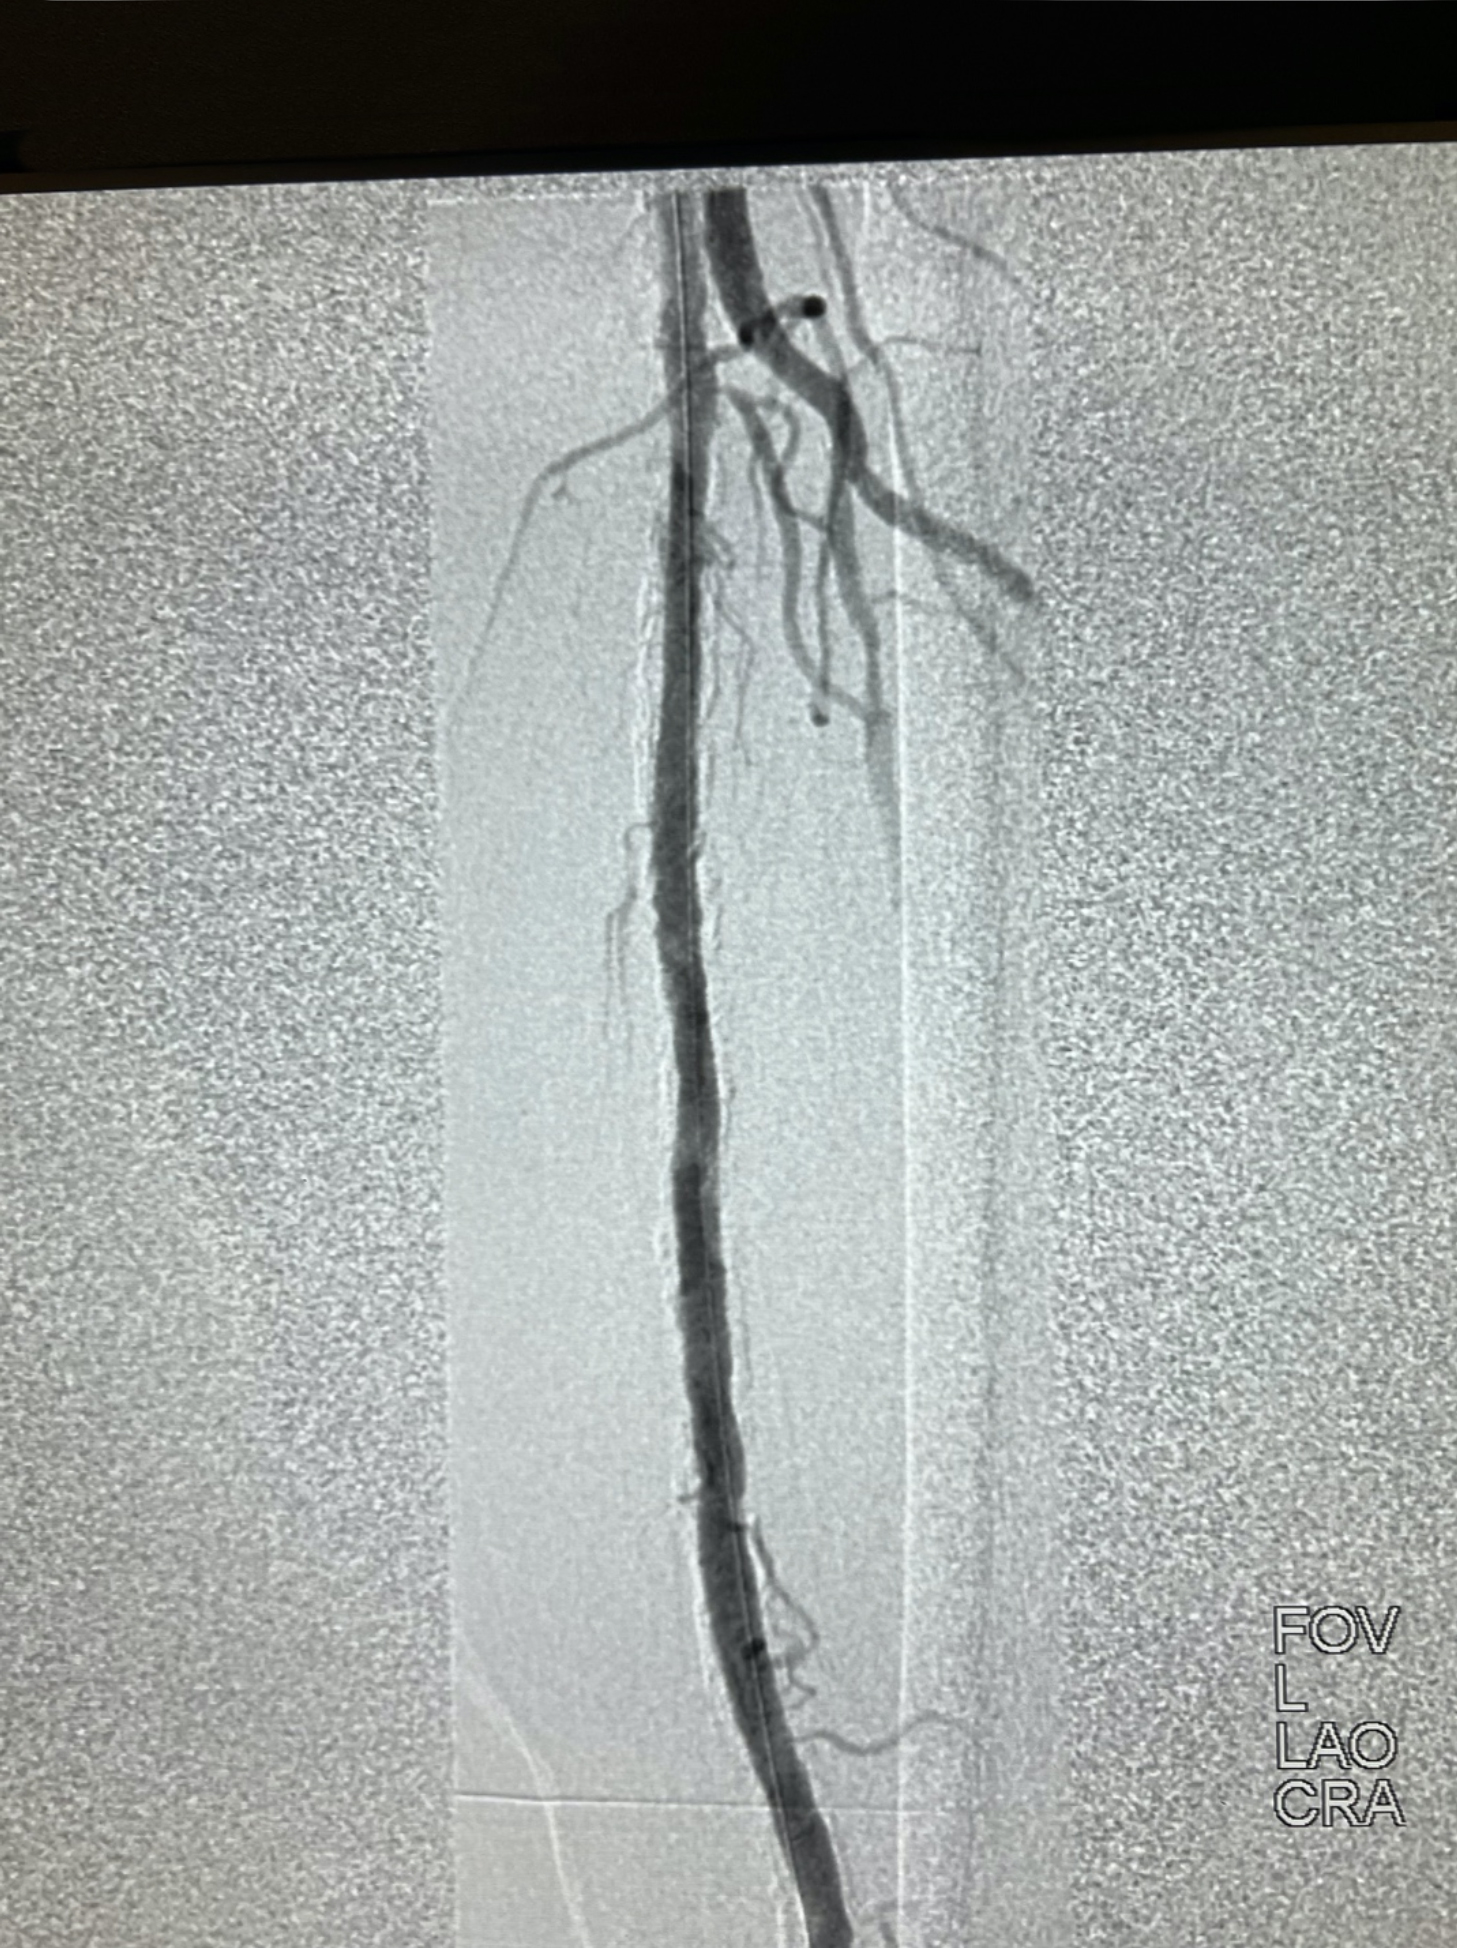

We obtained access of the right common femoral artery (CFA) under ultrasound guidance. We proceeded to perform an aortogram that showed that the inflow vessels were patent. Then a left lower extremity angiogram showed a chronic total occlusion in the left SFA (Figure 1). We started by placing a 7Fr x 45cm sheath up and over into the left CFA. We were able to cross the CTO with moderate difficulty. IVUS was then used to evaluate the plaque morphology and appropriately size the vessel. Given the extent of calcification we decided to use a 7mm x 60mm Shockwave M5+ balloon to perform IVL (Figure 2 and Figure 3). We followed this with DCB angioplasty with a 7mm x200mm Ranger (Boston Scientific). Follow-up angiography showed excellent flow with no residual stenosis (Figure 4). We were satisfied with the results and terminated the procedure. The patient did very well during and after the procedure. He was seen in follow-up and his ulcer is almost completely healed.